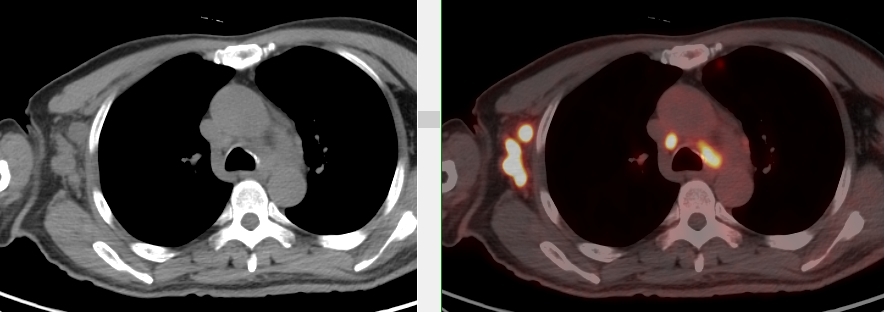

完善胸部強化CT考慮縱隔MT并縱隔、右腋窩及雙肺門多發腫大淋巴結,后行超聲引導下行右腋窩腫物穿刺活檢術,病理首先考慮惡性腫瘤,因穿刺組織局限,腫瘤細胞成分過少,不能明確診斷。

完善PET/CT檢查示:右側腋窩、雙側中下頸部、縱隔、雙側肺門多發MT,建議淋巴結活檢。后患者行右腋窩淋巴結切除活檢術,經北京大學第三醫院病理科會診示:右腋窩淋巴結惡性腫瘤,呈淋巴竇內生長模式,瘤細胞呈上皮樣,異型性明顯,伴中性粒細胞浸潤。結合病史及免疫組化,考慮為SMARCA4(BRG1)缺失的胸部腫瘤,伴神經內分泌標記表達。

本例為罕見病理類型的腫瘤,影像學表現無明顯特異性,診斷困難。強化CT和穿刺病理已基本明確為惡性腫瘤,行PET/CT檢查一是為了全身檢查,完善分期,二是根據PET代謝情況指導進行生物靶區活檢,進一步明確病理診斷。最終,PET/CT除縱隔病變外發現更多頸胸部淋巴結代謝異常,綜合考慮后對腋窩淋巴結進行切除活檢,最終得到病理證實。